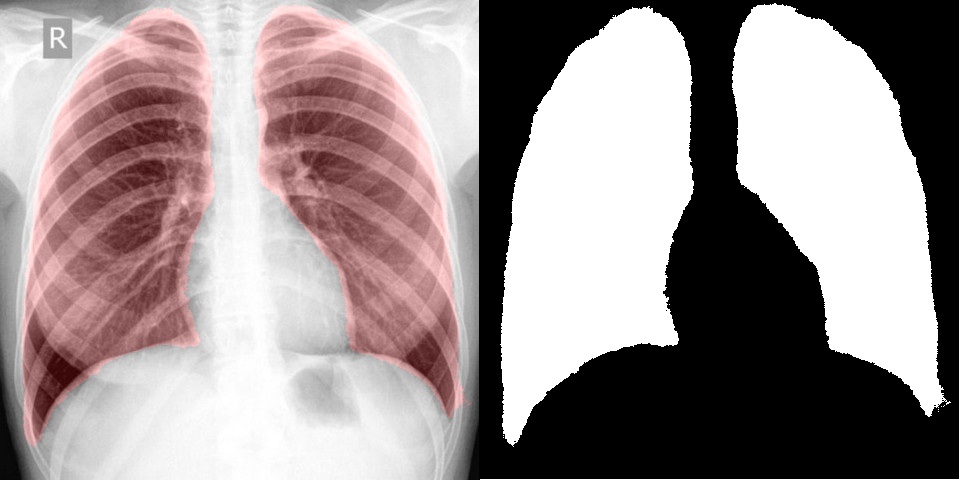

А что если попробовать что-то более необычное, интересное и сложное, например выделение и сегментацию на медицинских изображениях. Для теста снимки флюорографии были взяты с открытой базы КТ и X-RAY снимков, по ним было проведено обучение сегментации легких и в результате удалось достаточно точно выделить интересующую область. На вход сети также подавалось исходное изображение и маска с нулем и единицей. Справа результат, который выдает сверточная сеть, а слева выделена та же область на изображении.

Например, в статье используется модель легких для сегментации. Полученный с помощью сверточных сетей результат нисколько не уступает, а в некоторых случаях даже лучше. При этом, обучить сеть занимает куда быстрее, чем создавать и отлаживать алгоритм.